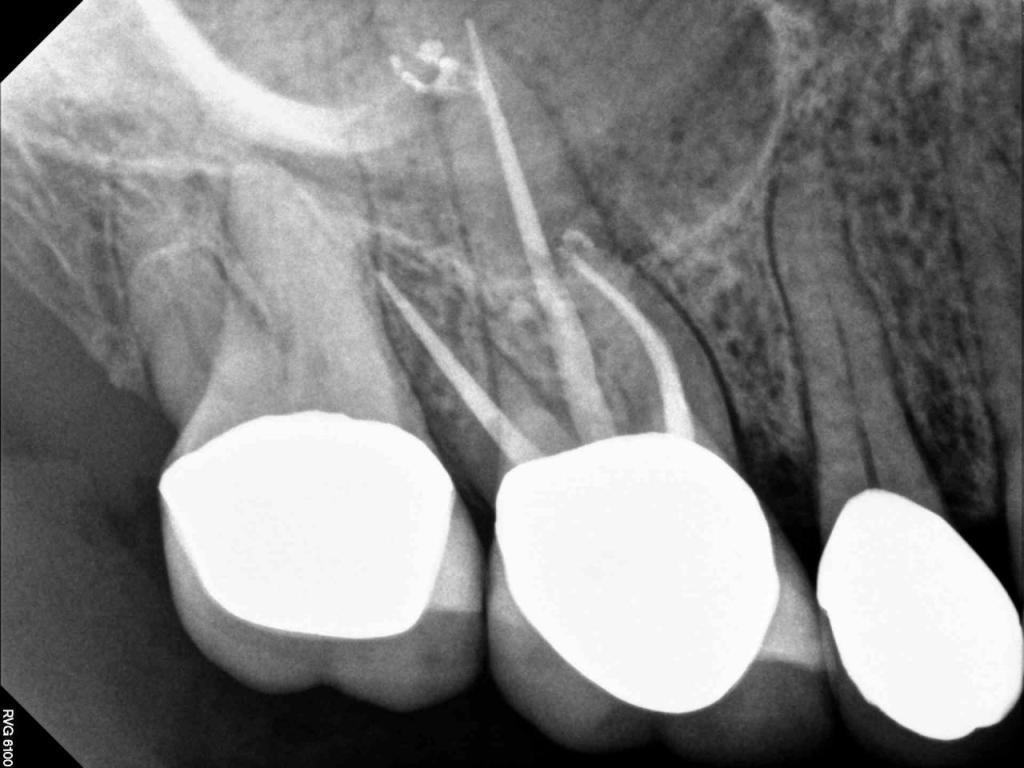

Although the primary use of visual documentation is for patient charts, dental images provide a meaningful way to communicate with patients about their care needs. Digital imagery is a vital tool for educating patients and an essential way to share information with office staff, colleagues and referring doctors. Digital technology has allowed Southcenter Endodontics to enhance our practice and improve the delivery of care to our patients. Below you will see images of “Before” and “After” scenarios. By clicking on a thumbnail image below, you will be able to see and a larger view of the x-ray taken at Southcenter Endodontics and notations made regarding each film.